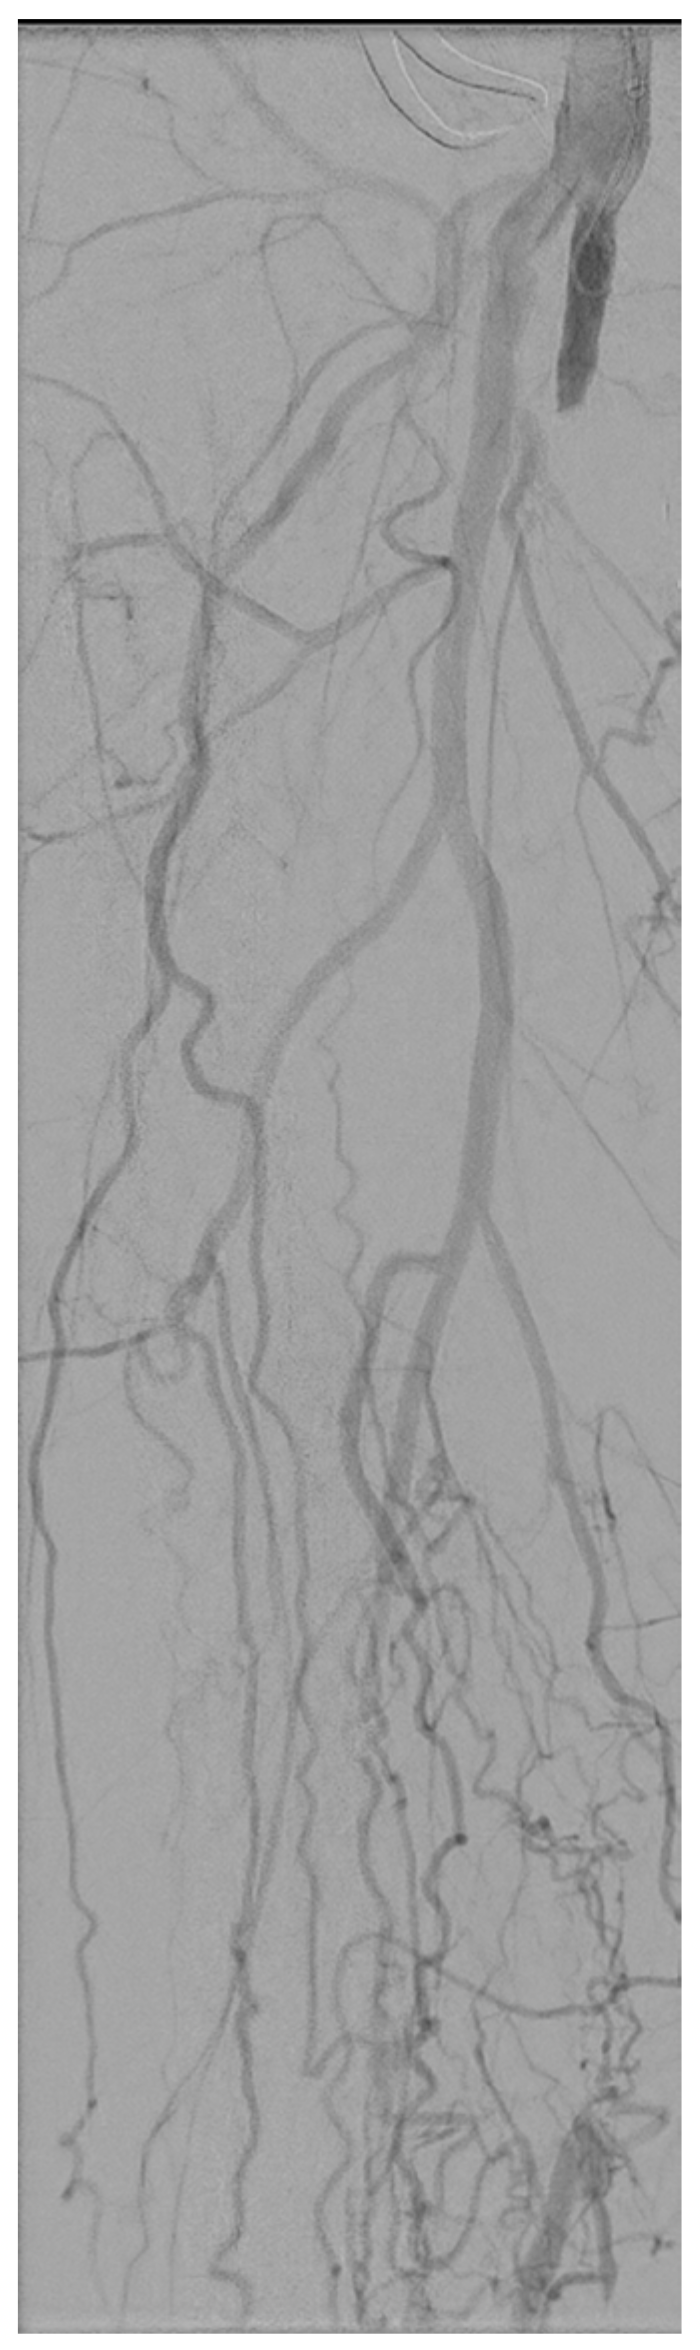

2. Case Report